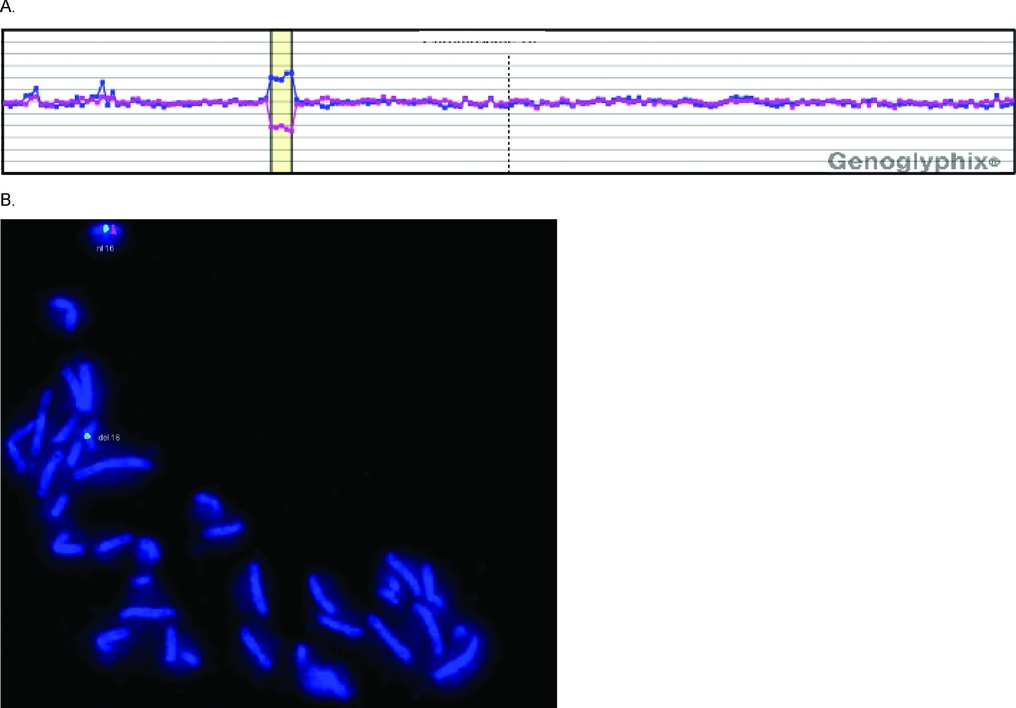

Results of genomic analyses. (A) Chromosomal microarray testing. The... Download Scientific Microarray Genetic Testing Fetus Acog and smfm published joint recommendations on the use of microarray in prenatal diagnosis in 2013. 13 cma is recommended when genetic analysis is performed in cases. Chromosomal microarray (cma) is a type of chromosome test that can be done during pregnancy along with an amniocentesis or. In prenatal diagnostic samples with a normal karyotype, chromosomal microarray will diagnose a. Microarray Genetic Testing Fetus.